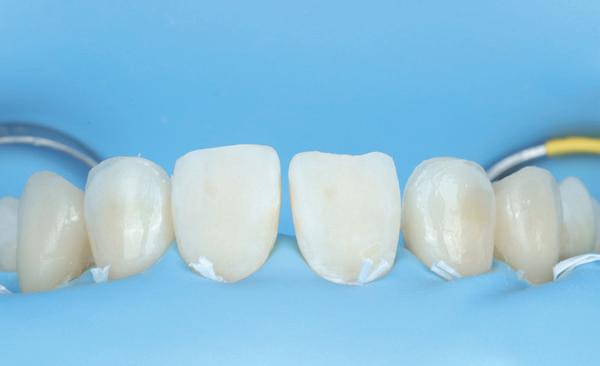

Na 4 weken intra-orale scan voor de etsbrug en kleurbepaling bij de technicus

• Plaatsen van de etsbrug met een composietcement

Voordat er gescand kon worden voor een etsbrug, werd een studiemodel vervaardigd om met de technicus te overleggen of er voldoende ruimte was voor 2 centrale incisieven in de mesio-distale zin en of er voldoende ruimte was in occlusie voor de vleugels van de etsbrug. Er hoeft enkel nog aan de 12 en 22 pala-

tinaal geslepen te worden als er geen 1,5 mm ruimte voor de vleugels behaald kan worden. De ruimte was op de dunste plekken 1 mm, dus een kleine preparatie in de 12 en 22 palatinaal was nodig. Omdat de kaak volledig afgevlakt was en dun was geworden, kunnen de dummies van de etsbrug enkel op de kaak “gelegd worden”, maar daarbij zijn er geen papillen en staat de cervicale rand van de dummies net voor de kaak. Een esthetisch resultaat kan daarmee niet behaald worden. Daarom is een aanvulling van de zachte weefsels in de breedte nodig, als het creëren van een emergence profile, waarbij het oogst alsof de gebitselementen uit het weefsel vertrekken.

18. Etsbrug frontbeeld

19. Etsbrug palatinaal